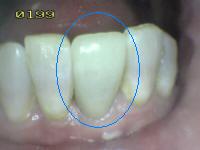

0 |

No obturado ni

sellado. |